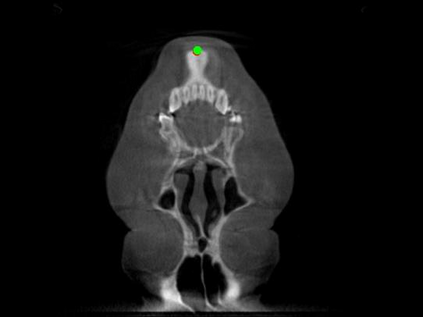

Detecting 3D landmarks on cone-beam computed tomography (CBCT) is crucial to assessing and quantifying the anatomical abnormalities in 3D cephalometric analysis. However, the current methods are time-consuming and suffer from large biases in landmark localization, leading to unreliable diagnosis results. In this work, we propose a novel Structure-Aware Long Short-Term Memory framework (SA-LSTM) for efficient and accurate 3D landmark detection. To reduce the computational burden, SA-LSTM is designed in two stages. It first locates the coarse landmarks via heatmap regression on a down-sampled CBCT volume and then progressively refines landmarks by attentive offset regression using multi-resolution cropped patches. To boost accuracy, SA-LSTM captures global-local dependence among the cropping patches via self-attention. Specifically, a novel graph attention module implicitly encodes the landmark's global structure to rationalize the predicted position. Moreover, a novel attention-gated module recursively filters irrelevant local features and maintains high-confident local predictions for aggregating the final result. Experiments conducted on an in-house dataset and a public dataset show that our method outperforms state-of-the-art methods, achieving 1.64 mm and 2.37 mm average errors, respectively. Furthermore, our method is very efficient, taking only 0.5 seconds for inferring the whole CBCT volume of resolution 768$\times$768$\times$576.